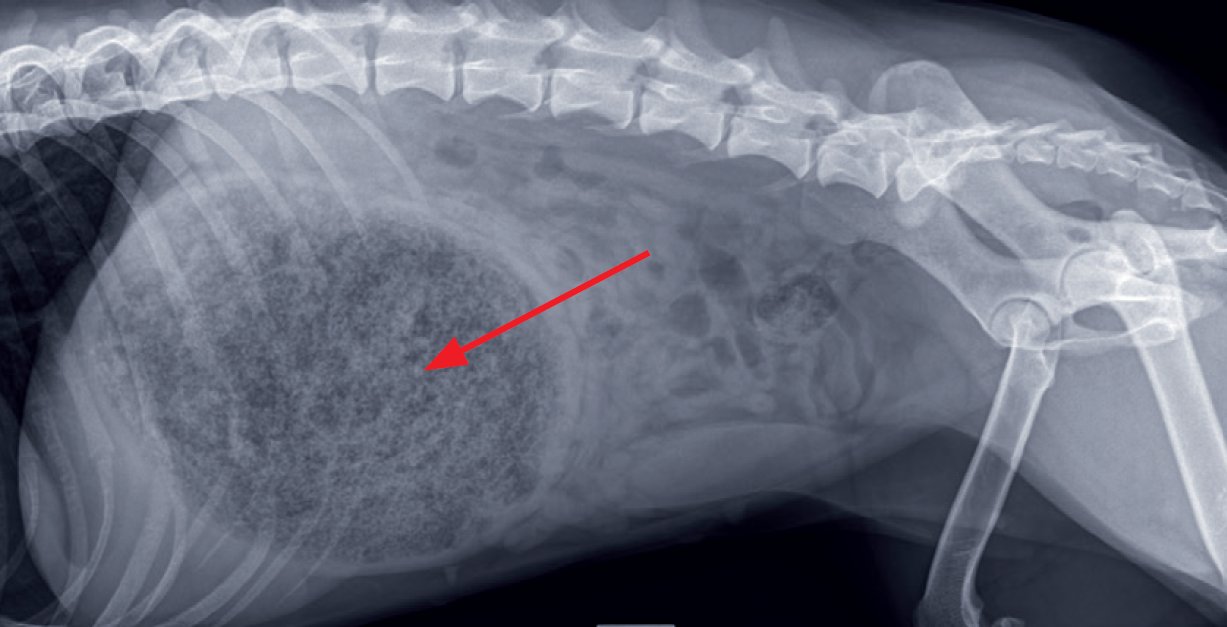

Photo n° 1B : Radiographie abdominale de profil.

Des radiographies abdominales orthogonales (photos 1A et 1B) sont réalisées.

Les radiographies abdominales mettent en évidence une silhouette stomacale hétérogène distendue avec un pattern tacheté/moucheté en son sein, un effet de masse en région crâniale est observé (photo n° 2).

Associées aux antécédents cliniques, elles suggèrent la présence d'un cyano-bézoard gastrique, formé à la suite de l'ingestion de colle, entraînant une obstruction du pylore et du cardia.